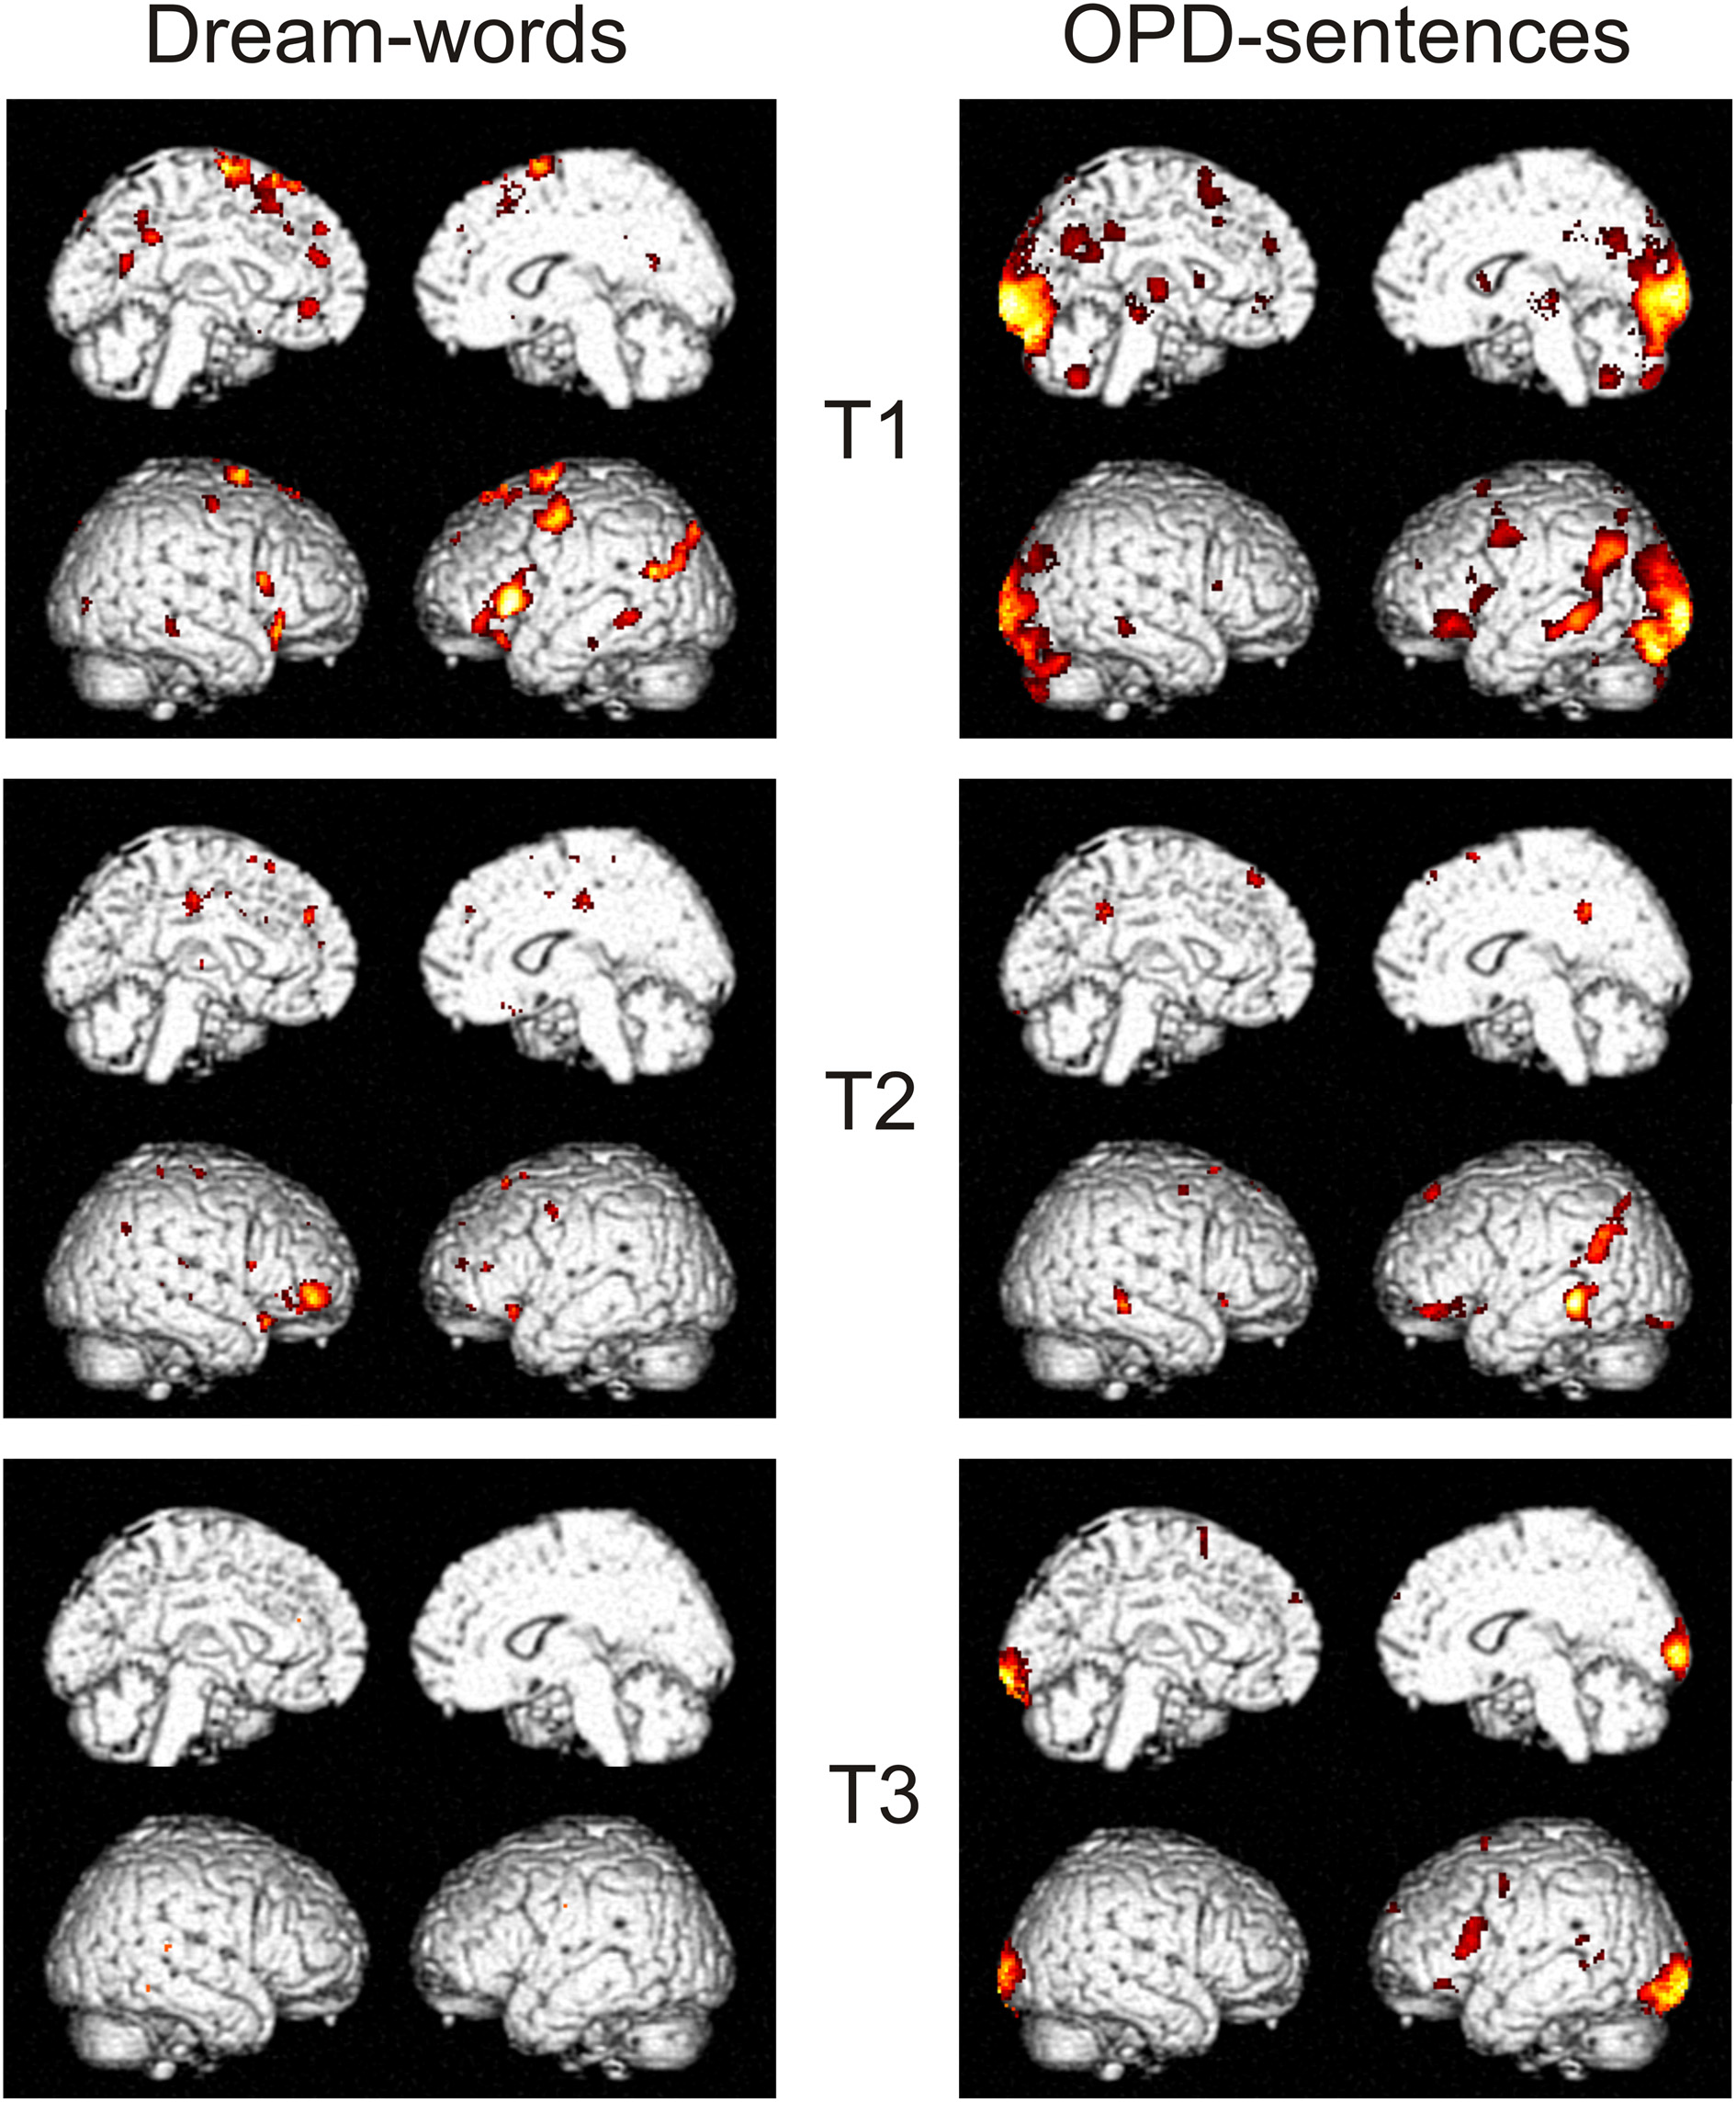

fMRI Data

Results of the dream-experiment revealed, that Dream-Words in contrast to Neutral-Words showed a differential activation. The contrast Dream > Neutral was significant in T1 and T2, but not anymore in T3 (see Figure 5). The contrast showed at T1 a widespread activation pattern in left inferior frontal (area 44 and 45), left superior frontal (area 6), left intra parietal cortex (angular gyrus, middle temporal gyrus), left middle occipital gyrus, right inferior frontal gyrus pars orbitalis, right temporal pole, left precuneus, left anterior cingulate cortex, left superior medial gyrus, right inferior frontal gyrus/pars orbitalis, right middle temporal gyrus, left superior medial gyrus, left medial frontal gyrus. From T1 to T2 this distinct pattern—being significant to emotional processing of the self—largely disappears. The complete disappearance of the pattern at T3 alludes to the assumption that the dream content has lost its special importance and is now experienced in the same manner as the neutral story (cf. Table 1). The calculated session-effect was significant (F = 6.8, p < 0.05 FDR, corrected for multiple comparisons).

Figure 5. T-contrasts Dream words > Neutral words (left side) and OPD-sentences > Relaxation (right) of a single subject (Subject Mrs A.) over time T1–T3, all thresholds to p < 0.05, T > 3.2, 10 voxels minimum, and corrected for multiple comparisons (FDR).

In the OPD-experiment the contrast OPD-sentences > Relaxation was significant at T1–T3 as well. The widespread activation pattern at T1 occipital (area 17 and 18), left and right hippocampus, left and right thalamus, left precuneus, left middle cingulated cortex, left inferior frontal gyrus/pars orbitalis, left precentral gyrus, vermis, left inferior frontal gyrus, right middle temporal gyrus, superior parietal lobule, cerebellum, and right and left putamen was markedly reduced at T2 and T3 (cf. Table 2). The calculated session-effect for this contrast was significant (F = 10.3, p < 0.05 FWE, corrected for multiple comparisons).

Both experiments distinctly showed a marked decrease of activation, lower pattern differentiation and even partial disappearance of patterns in the course of time from T1 to T3. In order to know whether or not the evolution of this pattern of activation from T1 to T3 is related to psychotherapy, it is needed to compare patients' data with control subjects' data. The data found thus far do not contradict this notion.